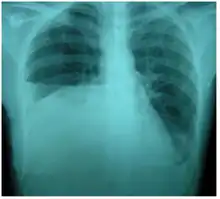

Chest X-ray showing urinothorax disappearing after treatment

Treatment mainly consists of treating the underlying disorder of the genitourinary tract.[2] It requires a multidisciplinary team that includes a pulmonologist and urologist. A nephrostomy tube or Foley catheter can be used to relieve any underlying obstruction. Any injuries are repaired.[11] When the underlying disorder is addressed, the urinothorax rapidly resolves. Thoracic surgery is usually not needed,[4] especially if respiratory symptoms are minimal or nonexistent.[2] Pleurodesis is also ineffective.[11] A chest tube can be used to drain urine from the pleural cavity.[12]